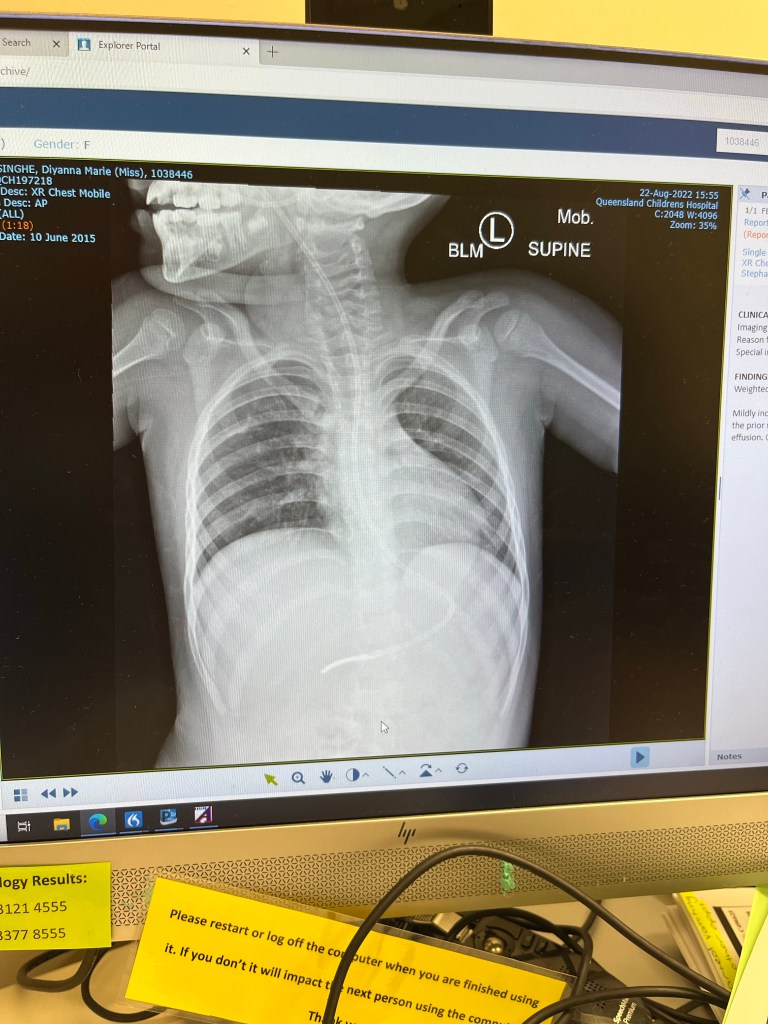

An x ray taken in the middle of the therapy showed some improvement in her right lung. Another would be taken in August. Towards the end of the steroid program Diyanna got covid 19. But she managed to pull through without needing a hospital visit.

In the lead up to meet Dr Kilner in August another x-ray was taken. And we received the new we had been waiting for. The inflammation in Diyanna’s lung had subsided to the point where there was no trace of it on the x ray. Until another bronchoscopy is carried out the extent of the internal damage is not known but we can be hopeful that the outlook is not as bad as what it was a year ago.

Unfortunately, her team still has no clue as to what triggered the inflammation. One thing that they did say was that Diyanna can slowly start oral feeds if she has the right equipment as the evidence doesn’t show continuous aspiration. According to her team this was most likely caused by substantial single event aspiration or pseudomonas infection or a combination of both.